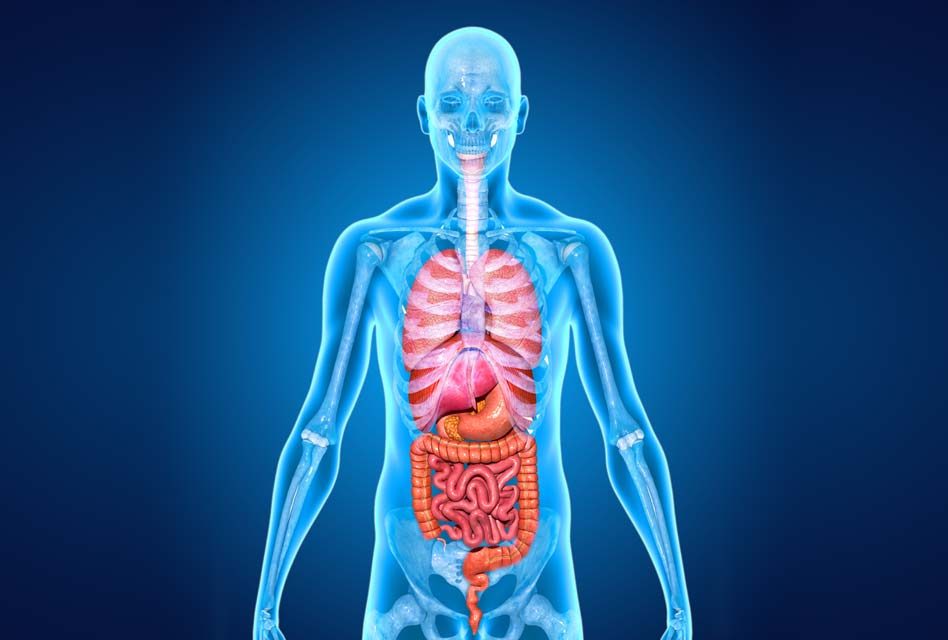

Изображения и визуализация внутренних органов человека